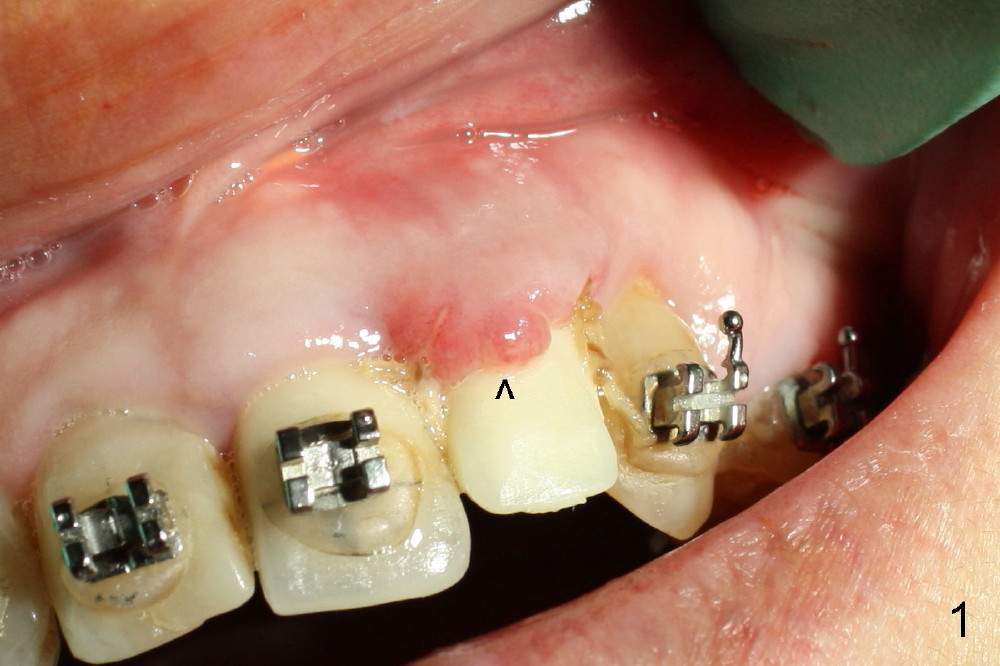

A prominent feature of implant failure in this case is pain. The patient feels that the pain is from the base of the nose. PA taken 3 days postop shows that the implant is inferior to the nasal floor (Fig.2 red ^). Clinically, the buccal gingiva continues to be erythematous 10 days postop (Fig.1). The pain is so unbearable that the implant (3.8x14 mm) is removed 10 days post placement. After repeated debridement, a 4.1 mm tap (Fig.3 T) is manually inserted with torque. A 4.1x14 mm submerged implant is placed with insertion torque < 30 Ncm, but it is placed subcrestally (Fig.4 <--). This time an immediate provisional is not provided. The flap is sutured. The pain disappears immediately. No infection is found 7 days postop (Fig.5). However, an asymptomatic vesicle is noted at the crest 3 weeks postop (Fig.6). The gingiva looks normal 2 and 3 months postop (Fig.7,8). The coronal gap dissolves 3 months postop (Fig.9 >, as compared to Fig.4), suggesting osteointegration. The implant is uncovered 4 months postop (Fig.10). Bracket is placed 5 months postop (Fig.10'). One month later, the left central incisor improves in position coronocervically (Fig.11), but the overjet needs correction by distalization of the upper anterior teeth. The implant at the site of #10 may be used as an anchorage.